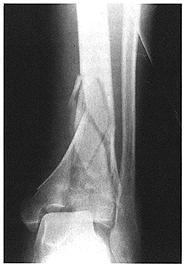

2. CLASIFICACIÓN SEGÚN SU PATRÓN DE INTERRUPCIÓN

1. según

1. continuidad ósea

1. se dividen en

1. FRACTURAS INCOMPLETAS

1. línea de fractura no abarca todo el grosor del hueso

1. - Fisuras -Fracturas de tallo verde - fracturas de caña de bambú o en torus

2. FRACTURAS COMPLETAS

1. Existe continuidad y afecta todo el grosor del hueso y periostio

1. Divide en

1. Fracturas completas simples

1. Tienen un trazo único y no hay desplazamiento

2. Fractura completa con desplazamiento

1. Son las que pierden la alineación de los fragmentos y dependiendo de su localización